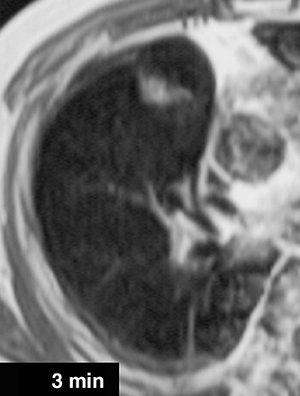

![]() |

| A 68-year-old woman with focal organizing pneumonia in right middle lobe of lung. Above, dynamic MR image before IV injection of gadopentetate dimeglumine. Below, dynamic MR image obtained three minutes after IV injection of gadopentetate dimeglumine shows slightly heterogeneous enhancement that is strongest in early phase (three minutes = time at maximum enhancement ratio). Signal intensity before and three and six minutes (time at maximum enhancement ratio plus three) after contrast injection was calculated by each region of interest. Maximum enhancement ratio, 126%; slope, 42%/min; washout ratio, 15%. |